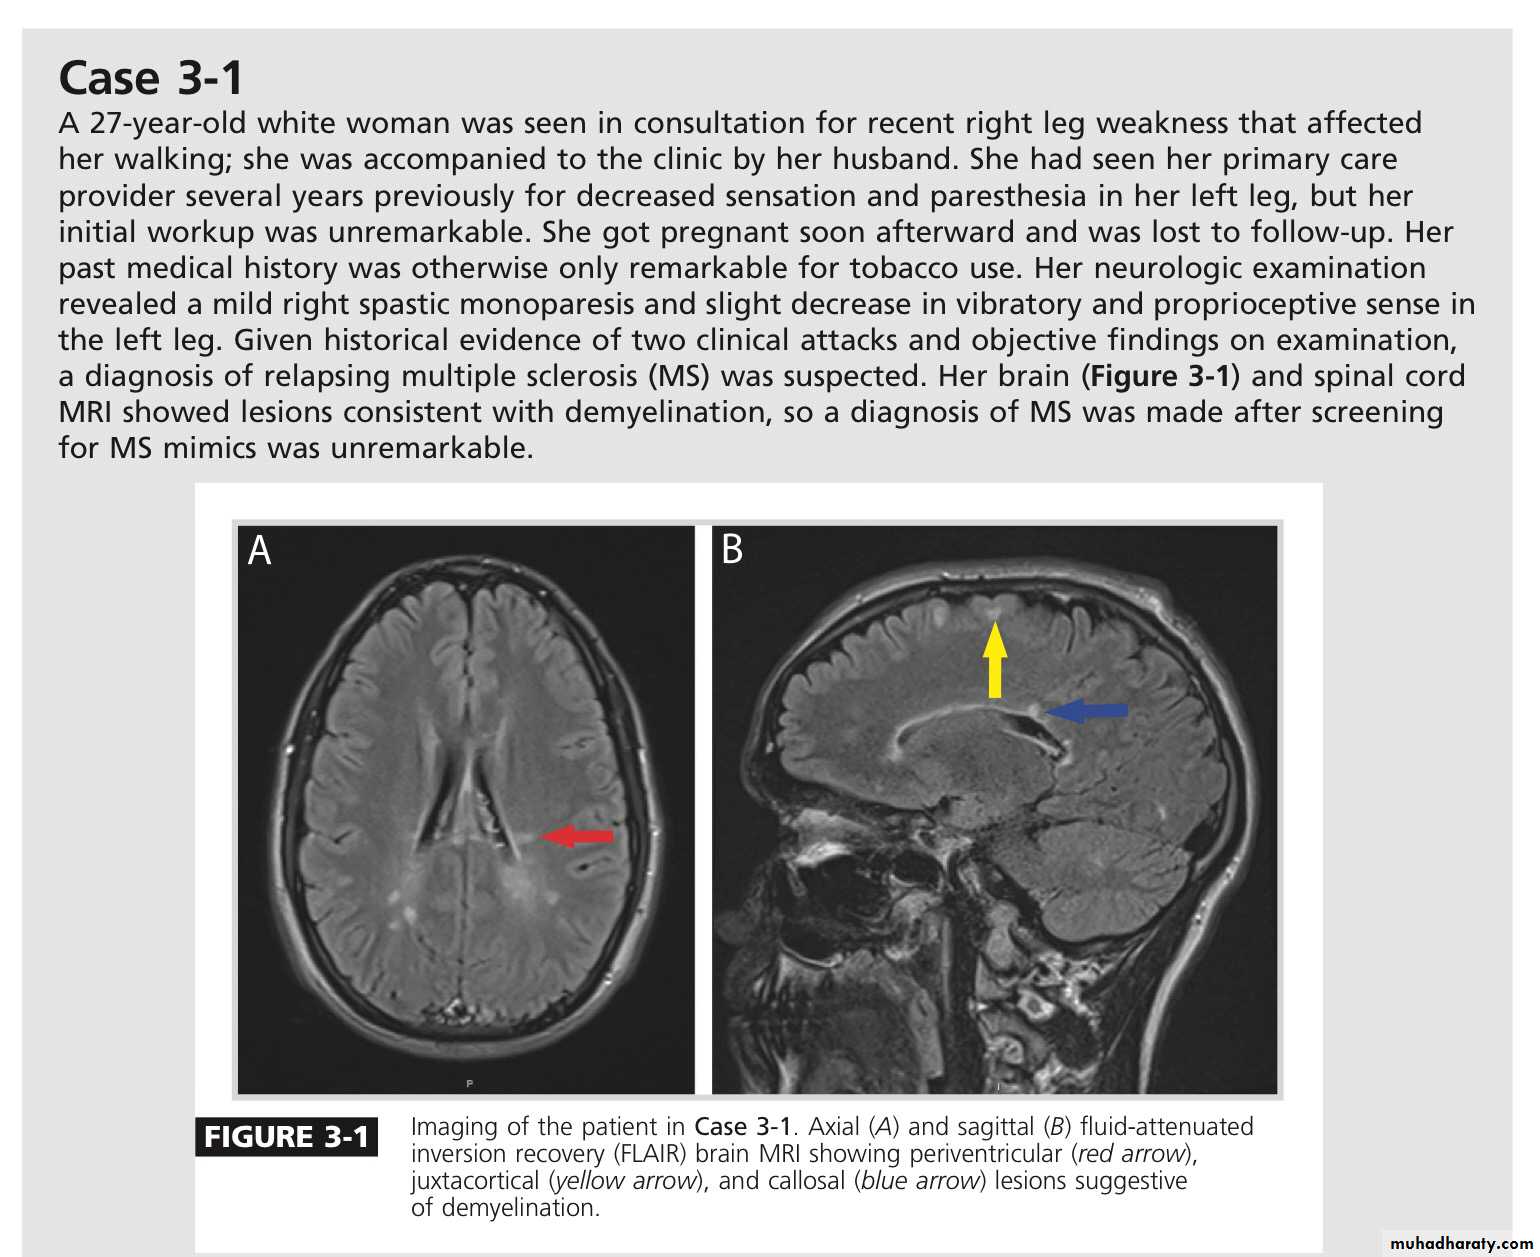

There is no definitive diagnostic test for MS. Diagnostic criteria for clinically definite MS require documentation of two or more episodes of symptoms and two or more signs that reflect pathology in anatomically noncontiguous white matter tracts of the CNS

MRI :characteristic abnormalities are found in >95% of patients, although more than 90% of the lesions visualized by MRI are asymptomatic

Lesions are frequently oriented perpendicular to the ventricular surface,(Dawson’s fingers)

Lesions larger than 6 mm located in the corpus callosum, periventricular white matter, brainstem, cerebellum, or spinal cord are particularly helpful diagnostically